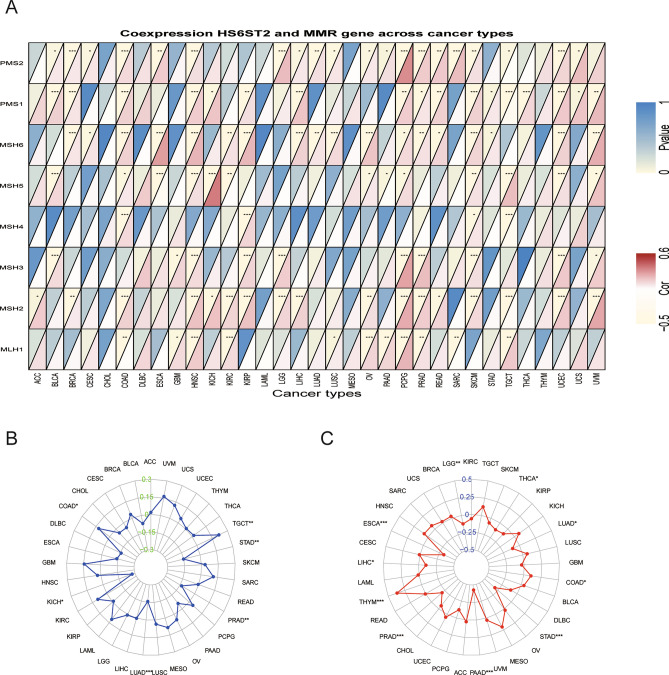

Correlations of MMR gene expression, MSI status, and TMB with HS6ST2 expression levels

DNA replication will produce errors; however, MMR genes can identify and correct such errors31. Due to abnormalities in the MMR mechanism, tumors with high MSI are more likely to accumulate many mutations in cancer-associated genes and develop a high TMB32. Consequently, we investigated the correlations between HS6ST2 expression and MMR genes. MMR gene expression was strongly favorably connected with HS6ST2 expression in almost all cancers (except cholangiocarcinoma and acute myeloid leukemia) (Fig. 7A, Supplementary Table S1). In six types of tumors (lung adenocarcinoma, prostate adenocarcinoma, stomach adenocarcinoma, testicular germ cell tumors, colon adenocarcinoma, and kidney chromophobe), HS6ST2 expression was related to MSI status, as presented in Fig. 7B. TMB was significantly linked with HS6ST2 expression in esophageal carcinoma, thymoma, prostate adenocarcinoma, pancreatic adenocarcinoma, stomach adenocarcinoma, brain lower grade glioma, liver hepatocellular carcinoma, colon adenocarcinoma, lung adenocarcinoma, and thyroid carcinoma, as shown in Fig. 7C. Our findings imply that HS6ST2 participates a role in mediating cancer via regulation of DNA damage.